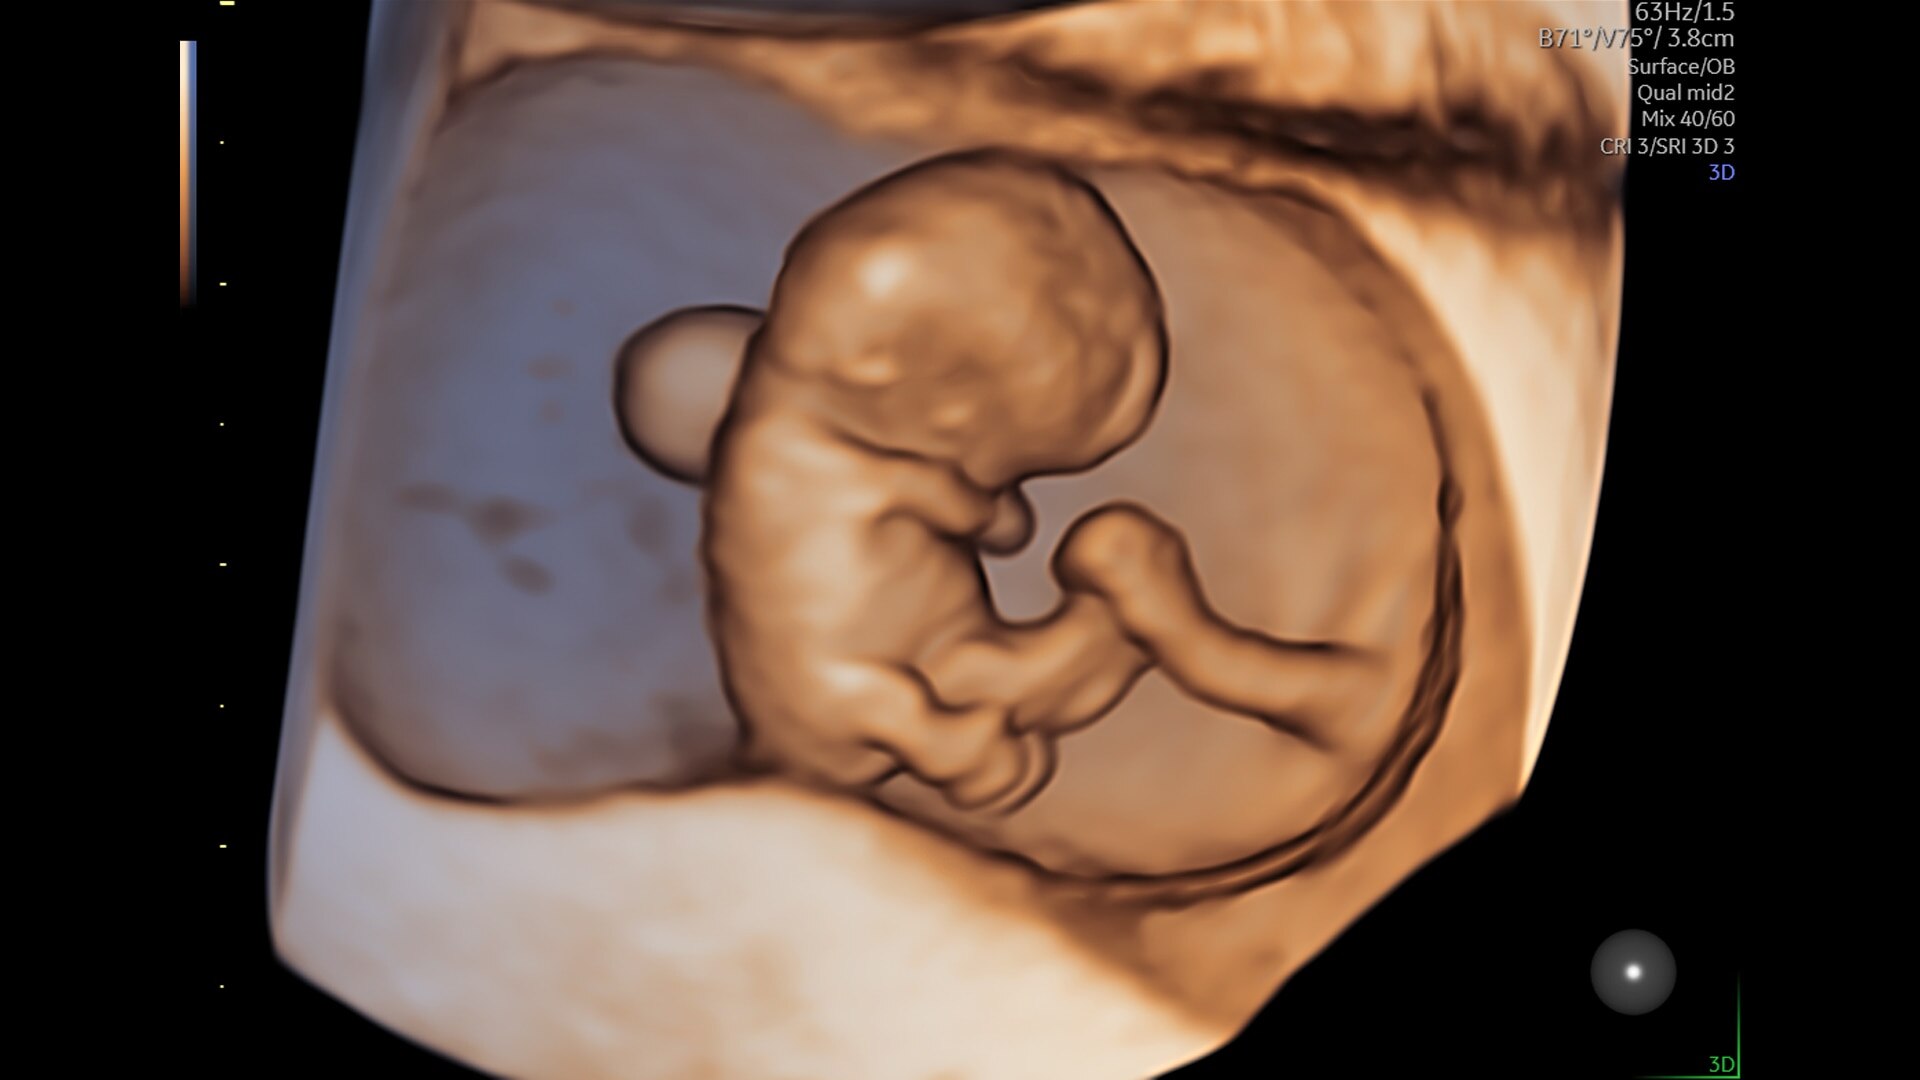

Voluson Unity Architecture

Get great images fast.

Advanced beamforming capabilities work in harmony with expert-level probes to deliver faster processing speeds and frame rates for enhanced detail and contrast resolution, greater color quality and sensitivity, and exceptional 3D/4D.